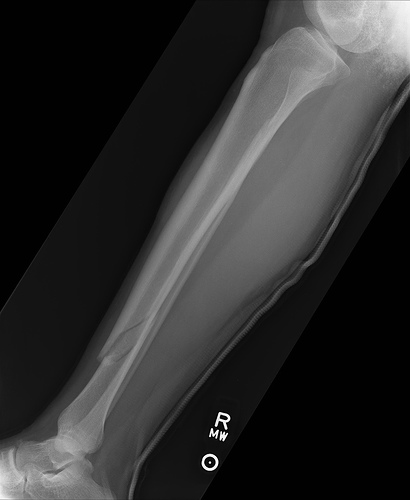

Seattle Police say a man called 911 Friday afternoon after finding what appeared to be a human leg bone on the roof of a warehouse. According to police, the disturbing call came in around noon directing authorities to the 2600 block of NW Market Street.

The man who made the grim discovery also told police he did not believe the leg bone belonged to an animal.